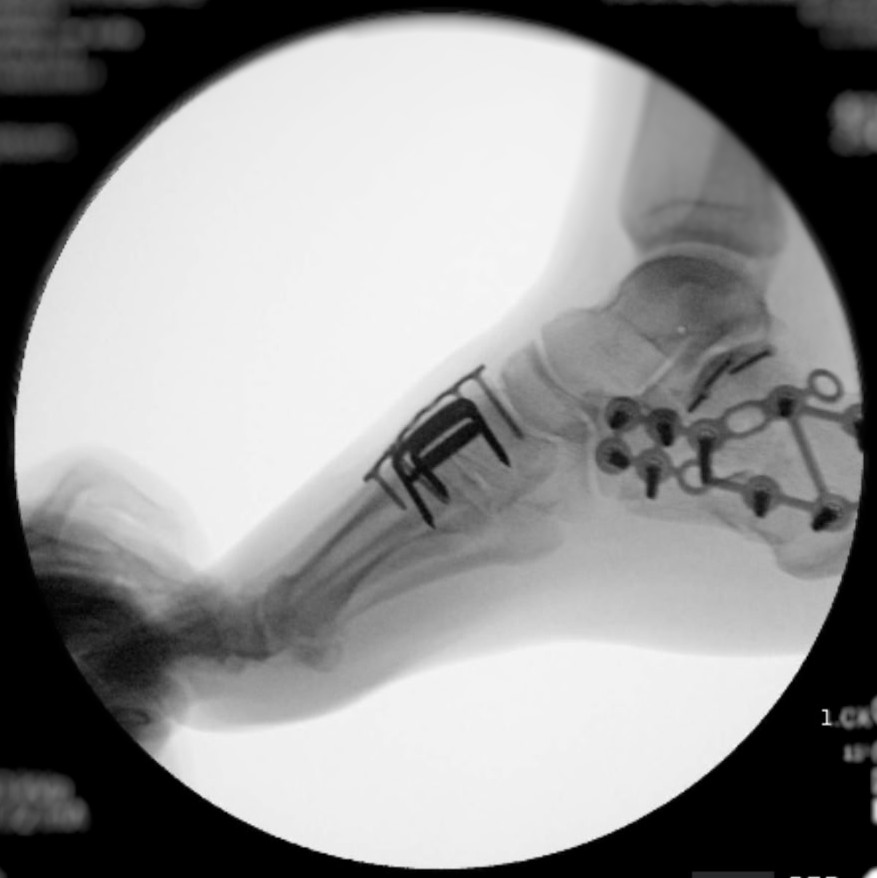

Hello, I am sure many of you have heard the news of Anita Featherstone (Morris) being involved in a head-on accident with a drunk driver. On Sunday afternoon, March 30th, she was leaving the Crosby/Houston area, heading to visit her daughter and grandsons. She was driving and missed her turn, and she was rerouted down a two-lane road she doesn't normally travel. As she was driving, she saw a car headed towards her in the other lane. She saw his tire slip off the road, and then everything went black. The next thing she remembers is waking up in the car (thinking she was dying). She was struggling to breathe and was in severe pain. With the help of a "good samaritan" that yielded, he was able to help her get out of the car and contact her family. She was not able to walk as part of her foot was missing with the bone exposed. Her sons (Michael & Matthew) arrived at the scene moments later and were informed by the responding officers that she was hit by a drunk driver and would need to be airlifted to Memorial Hermann Medical Center. She arrived at the hospital and was immediately rushed to trauma where they performed X-rays and CT scans to determine the extent of her injuries. She sustained major injury to her right foot and hand, with her right foot having a compound fracture with the heel crushed and her right hand also fractured. They were able to splint her hand but required emergency surgery on her right foot. She had many other contusions and bruises all over her body. She went into surgery several hours later where they cleaned out the wound, performed a nerve block, and set the foot. This is only step one in a very long road to recovery. She will need to have at least two more surgeries on her right foot. Her next surgery will not happen for at least two weeks because the swelling must go down. She is not able to put pressure on her right foot for two months. She will require physical and occupational therapy to learn how to walk again. Due to the nature of the injuries, she will not be able to use a walker, crutches, or a scooter for a couple of months. Unfortunately, the individual that hit her was driving an unregistered vehicle without insurance and has no license. He also was undocumented. Thankfully, they confirmed with blood tests that he was intoxicated, and Harris County will be bringing charges. Anita is self-employed and will not be able to work for months, and her medical bills are already piling up. Anything you can give would be much appreciated. Thank you all for hearing our story. God bless.